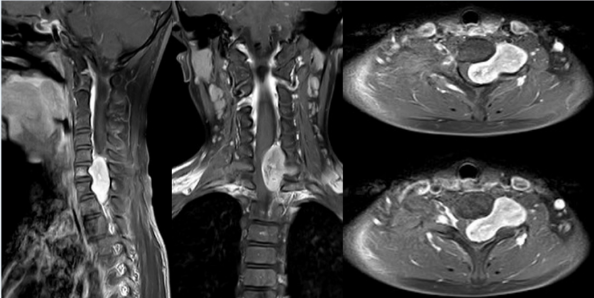

据了解,患者李明明(化名)今年10岁,半年前出现走路不稳容易跌倒,左手无力握物不稳。在当地医院⾏颈椎MRI检查提⽰颈椎管内肿瘤,其⽗母拿到结果后惊慌失措,知道此病非同小可,听闻中南大学湘雅三医院脊柱外科在脊柱肿瘤诊治⽅⾯有着丰富的经验,便慕名前来。

患者所患肿瘤位于C5-T1平⾯椎管内,椎管80%空间已被肿瘤侵占,颈段脊髓受压非常严重。如肿瘤继续生长或者轻微外伤,患者就会完全性截瘫,犹如颈部被安放了一颗炸弹,一旦引爆,后果不堪设想。

湘雅三医院脊柱外科邓幼⽂教授、臧晓方教授、王剑龙教授、王卫国主治医师,及神经外科王知非教授、吴光勇副教授、颜辉主治医师等,联合肿瘤科专家、医学影像专家迅速启动MDT诊治模式,对患者的病情进⾏了详细的评估。通过完善增强三维CT、增强核磁共振、数字化3D肿瘤模型,彻底摸清肿瘤和周围神经、血管、骨骼的毗邻关系,制定了详尽而周密的⼿术计划——完整切除肿瘤并防止误伤颈部神经血管。